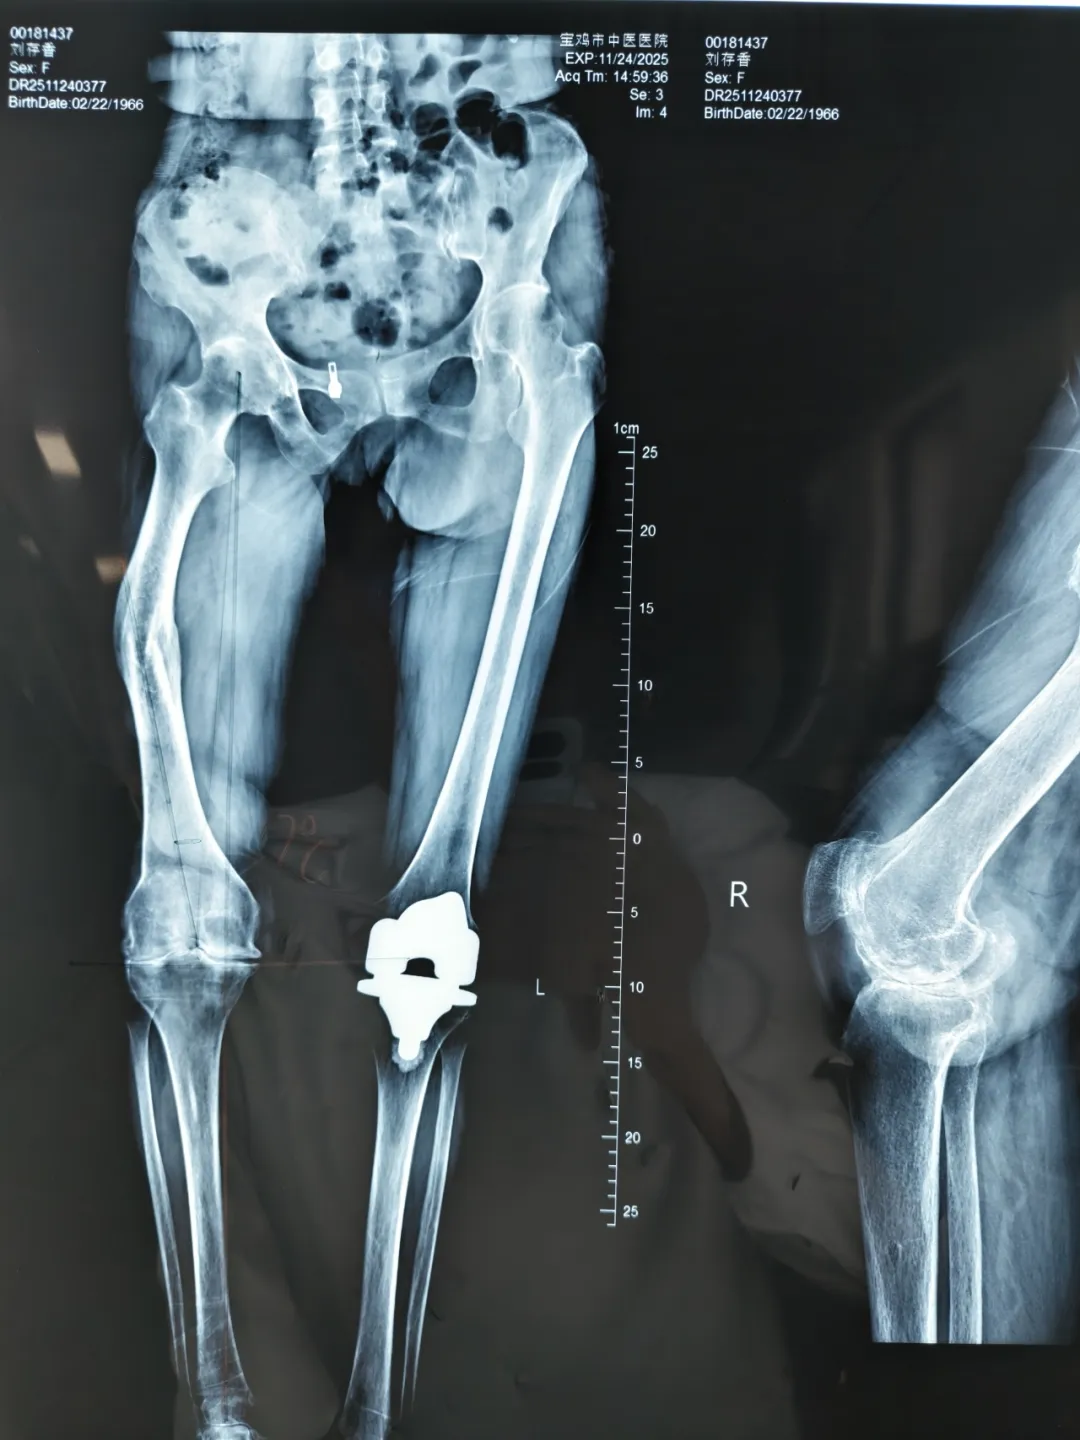

术前X线片

右膝关节置换术后X线片